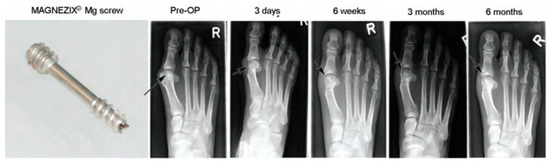

| Magnesium Alloy Material Types | Part | Sample Numbers | Country | Degree of Healing | References |

|---|---|---|---|---|---|

| Mg-Y-RE-Zr screws | Bunion correction | 13 | Germany | All healed | [202] |

| Mg-5 wt%Ca-1 wt%Zn | Internal fixation of fractures of the metacarpal and carpal bones | 53 | Korea | All healed | [68] |

| Mg-Y-RE-Zr screws | Bunion orthopaedics | 40 | Germany | 79% healing after 6 weeks, 90% healing after 12 weeks | [202] |

| Pure magnesium screws | Femoral head ischaemic necrosis graft tape; vascular bone flap fixation | 48 | China | No displacement or collapse of bone flap after operation | [69] |

| Mg-Y-RE-Zr screws | Bunion orthopaedics | 100 | Germany | All healed | [202] |